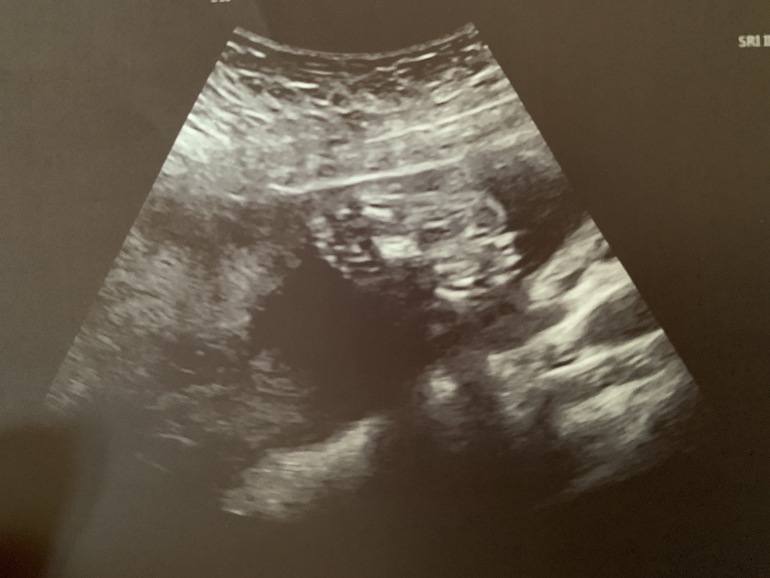

а это лапки👣